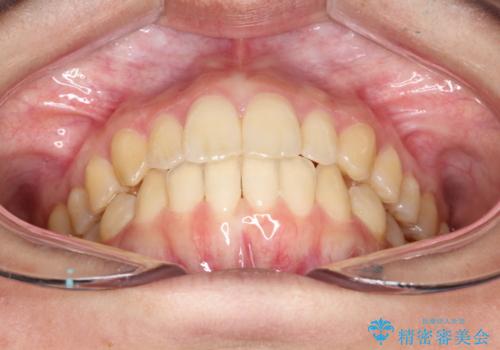

- 前歯が少し前に出ているのが気になるとのことで来院されました。

インビザラインにて上顎の歯を全体的に後方に移動させて前歯を引っ込める計画としました。

使用時間を守っていただけたので、比較的スムーズに矯正を終了することができました。